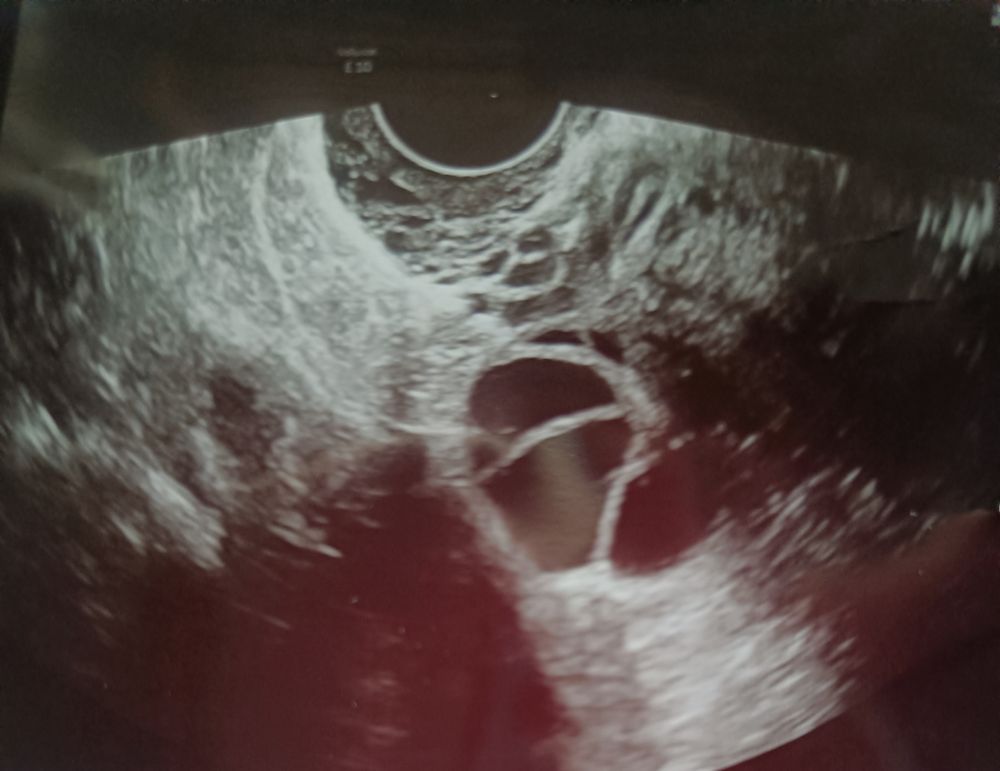

Не обращайте внимание не узи , пытайтесь . Мне тоже сказали что фоликулы не лопнули и овуляции в месяце зачатия у меня нет , выписали таблетки для стимуляции после мес, но мес так и не пришли. и Клеар смайлик не показал, итог видите сверху ) по узи дата зачатия совпадают с датами овуляции в календаре, когда я делала тесты и была на узи

Буду дважды мамой в этом году, меня на просто смутила перегородка, что за зверь такой, никогда раньше не было такого))

TSVETOCHEK, да понятно, врача смутила перегородка в нём, но она как то точно не сказала и в заключение УЗИ не написала ничего про нее) будем пробовать)

Есть шанс, что овуляция была? Плодное яйцо